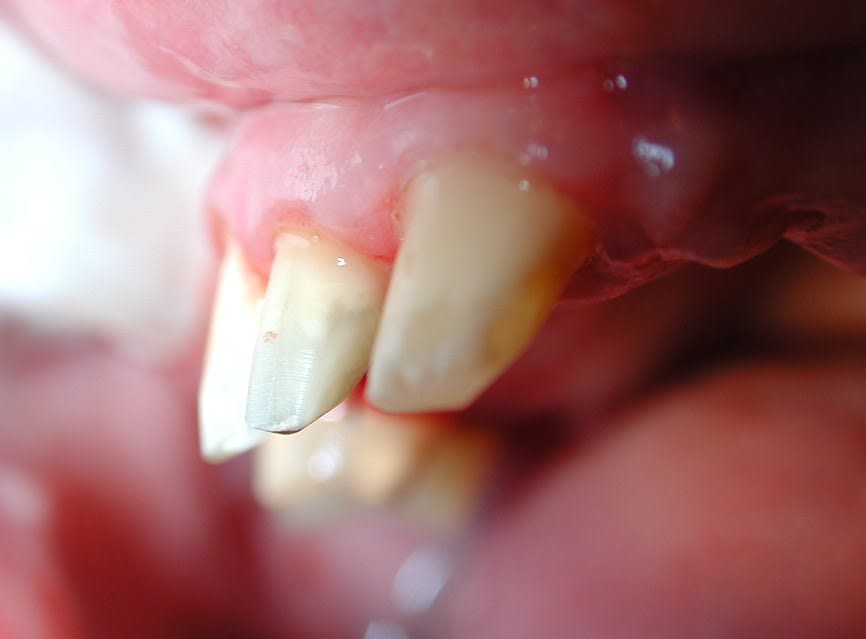

Lardonbis , tjs suite a ta question sur les limites mais en photo ,

voilà la taille de la page 25 , 1 semaine apres .

pourtant ,lors de la taille il n'y avait pas de fil , et la gencive pas trop touchée .

eh bien ,les limites apparaissent naturellement .

et donc avant de prendre l'empreinte , autant reprendre les limites ,et ç est là qu'intervient le fil .

et la taille du fil depend de la profondeur où tu veux placer ta limite . voilà pourquoi il y a plusieurs tailles :-).

et quand tu le mets il n'y a pas une goute de sang .

( là ça saigne pcq j'ai fait le compo mesial de 24 )

et donc apres finition des limites ça donne ça , et comme ça ne saigne pas ,on peut prendre l'empreinte .

et là la gencive sera stable ,comme sur la 22 ou j'ai posé une àmax il y a quelques années .